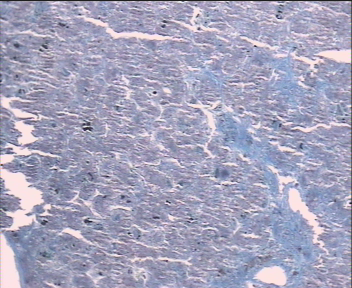

A case of neonatal hemochromatosis is reported in a premature 35-week infant who presented at birth with coffee ground vomiting and gradual appearance of grayish icter and colorless stool. Neonatal hemochromatosis was confirmed by elevated ferritin levels and extrahepatic siderosis detected in liver biopsy.